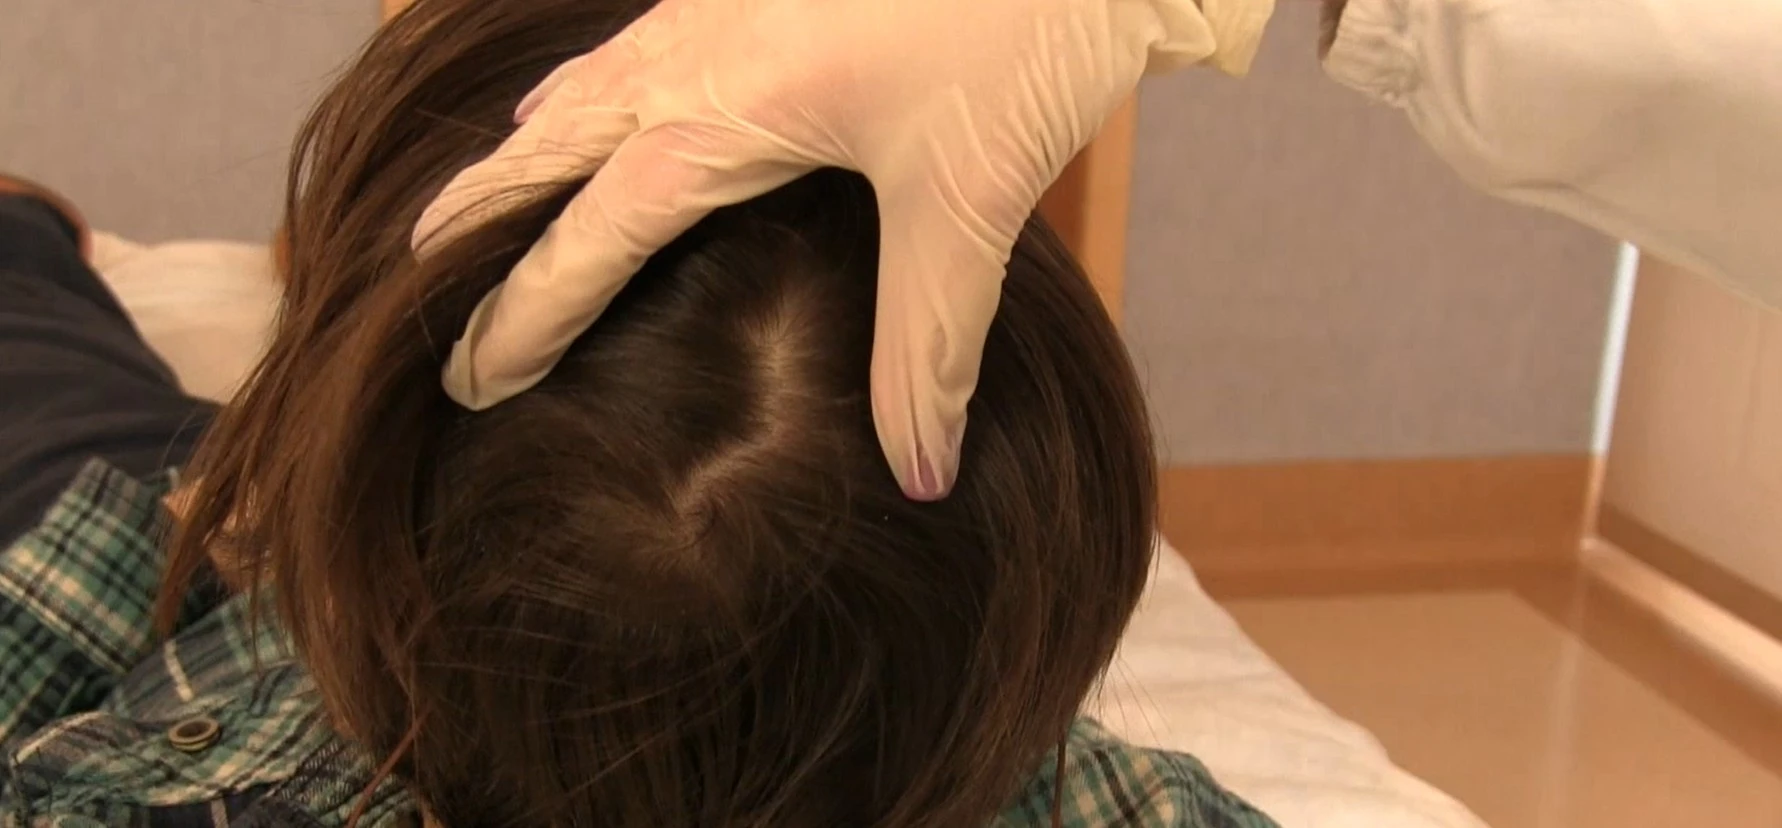

Lettura del Tracciato EEG – Oscurata

La procedura di acquisizione EEG evidenzia come la corretta gestione del tracciato e il riconoscimento degli artefatti siano fondamentali per garantire qualità e affidabilità dei dati registrati.